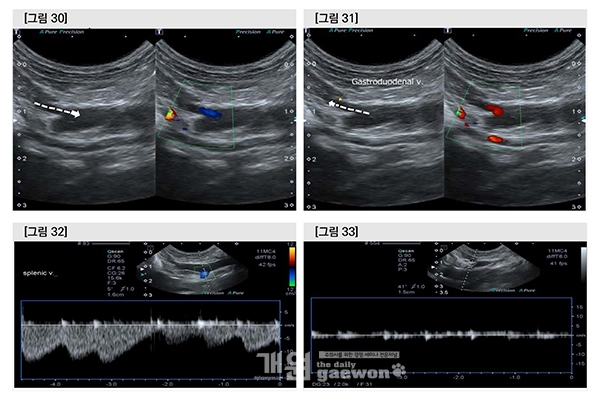

수술 이틀째 gastroduodenal v.에서 hepatofugal flow와 hepatopetel flow가 호흡에 따라 alternation 되고 있었으나 splenic v.에서는 consistent hepatofugal flow였고, 간으로 insertion 하기 직전의 portal vein을 flow velocity는 거의 측정되지 않았으므로 여전히 문맥혈액은 간을 우회(bypass)하고 있다고 판단하였다.